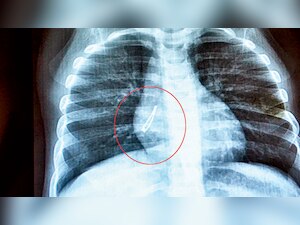

When seven-month-old Ariba Khan suffered from a cough and fever, her parents took her to the local physician thinking it was a routine illness. When the X-Ray showed a wire strand in her right bronchus, they thought she had swallowed a thread and the doctor advised them to wait till she passed it naturally through her stools.

But the doctors at Bai Jerbai Wadia Hospital in Parel were surprised when they fished out a LED bulb that the Chiplun-resident had swallowed while playing with a toy cell phone.

"Ariba was given antibiotics and steroids for three days to clear the infection and granulation of airway which blocked the bulb," said Dr Divya Prabhat, head of the ENT Department. "Then, a bronchoscopy was performed and within two minutes, the foreign body was removed using forceps. To our surprise, it was a 2 cm LED bulb."